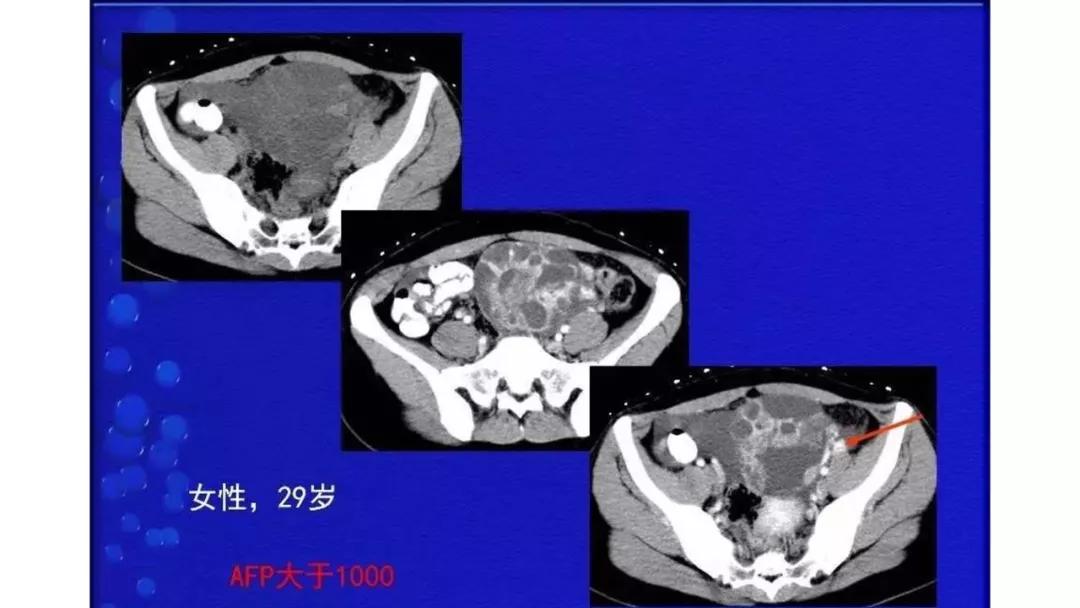

恶性者常呈实性或混杂性肿块,多数边界清楚,可伴有不规则沙粒状钙化。无性细胞瘤常为实性肿块,轻度强化,内胚窦瘤实性成分明显强化,不成熟畸胎瘤呈混杂密度。结合年龄及临床生化检查,有助于诊断。

AFP升高:卵黄囊瘤、无性细胞瘤、混合瘤